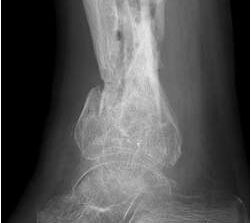

• Primäre oder posttraumatische Arthrose des OSG und USG (Abbildung 1, Abbildung 2).

• Pseudarthrosen (Abbildung 5, Abbildung 6).